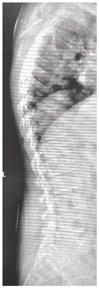

X线及CT检查:14例患儿影像学检查均存在异常,各部位X线检查均可见骨密度降低。长骨及手:干骺端明显膨大,其中以食指、中指掌指关节及近端指间关节远端受累显著(图3)。掌骨、指骨干骺端膨大14例、腕关节干骺端膨大7例、膝关节干骺端膨大8例;关节间隙狭窄6例,骨骺提前闭合及骨龄提前7例。骨盆平片表现为双髋关节间隙狭窄11例,股骨头骨骺扁平8例(图4A),股骨颈变短2例、股骨头外移4例,关节面硬化、囊变、骨质破坏8例。脊柱:椎体普遍变扁,上下缘形态不规则、前上下缘可见骨质缺损,椎间隙变窄、中后部明显,椎弓根变短(图5);颈椎受累1例,胸、腰椎受累13例。

由于髋部、膝及脊柱的变化导致身材矮小,病初患儿身高多正常,但终身高通常低于P3[2,18]。本研究有8例患儿表现为身材矮小。重症JIA特别是多关节型JIA,可以累及全身多个关节炎,导致残疾,合并生长发育障碍,导致身材矮小。故PPRD和JIA临床表现相似很难鉴别。PPRD患儿多存在脊柱受累表现,本研究中8例患儿有脊柱活动受限,3例表现为脊柱侧弯、2例表现为胸椎后凸,1例表现为胸椎前突,1例表现为颈椎活动受限,而多关节型JIA患儿脊柱受累较少见。脊柱骨骺发育不良影像学表现为椎体边缘粗糙,前端变扁变尖,呈子弹头样改变是PPRD最典型的影像学改变,也是和JIA最重要的鉴别点。因此对于以步态异常起病、髋关节受累严重的患儿应注意鉴别PPRD,完善影像学检查,特别是脊柱正侧位X线片,并行基因检测。根据典型的放射学改变和基因检测结果,诊断PPRD并不困难。